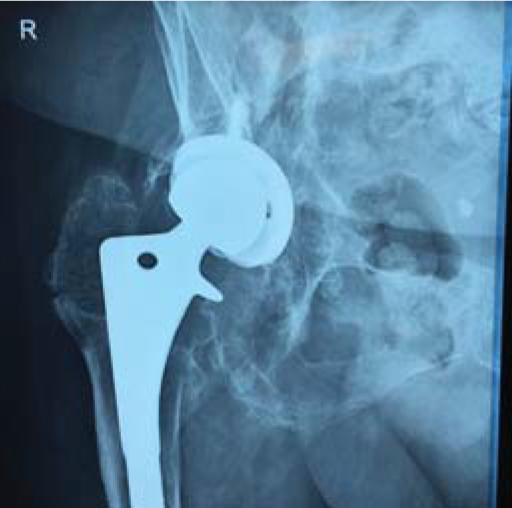

对患者进行CT扫描,以确定病体需切除部位。

此次医生根据患者病情决定使用3D打印技术完成手术方案,因该患者病体部位形状相对复杂,用常规技术手段手术极其困难。利用3D打印技术可按照1:1的比例打印出完全相同的原本病体部分,这可与病人身体完全契合,融为一体。

为患者手术用植入体进行进一步的优化和尺寸确认,为精确钻孔订制钻孔导向,为完成手术最佳效果定制螺钉旋转轨迹。对植入体再一步的尺寸确认。使植入体在生物力学结构、局部形态等方面,最大程度的模拟人体结构。

根据扫描结果重建,将数据传输至3D打印设备,按照1:1的比例打印出假体。选择此类永久性植入体时,保证其质量的稳定是最关键的一环。相关的经验和技术水平是评定一家3D打印企业的重点,而飞而康科技不论从哪个方面来说,绝对具有权威公信力。